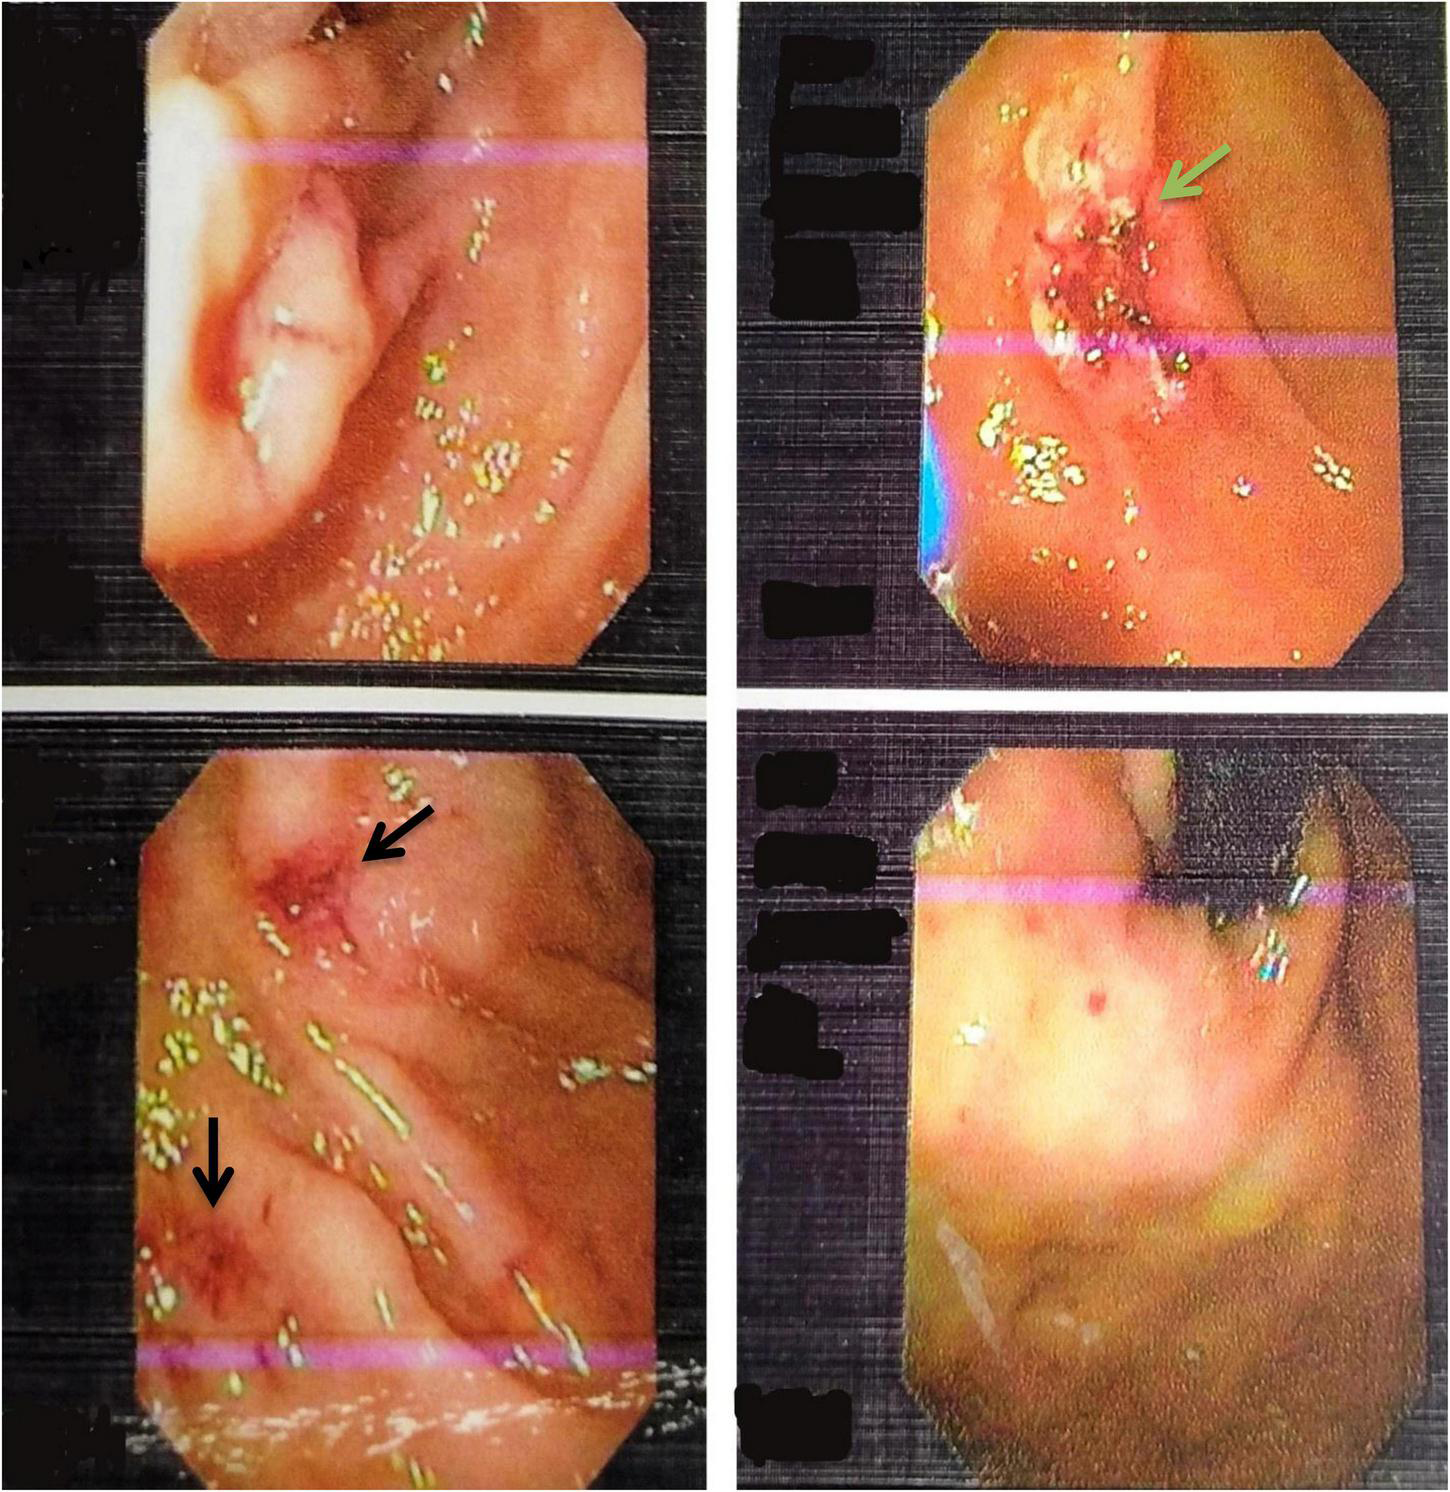

FIGURE 1

www.frontiersin.org

Figure 1. Upper Gastrointestinal endoscopy images showing multiple telangiectasia in the stomach (black arrows) and ulcer located in the second part of the duodenum (green arrow).

This 23-year-old patient with a positive family history of epistaxis in his (late) father had occasional episodes of epistaxis since childhood without seeking medical attention until adulthood (2016) when he presented with intermittent episodes of melena and severe generalized body weakness and palpitations. His lab investigations revealed positive fecal occult blood and very-low hemoglobin (Hb) of 4.6 g/dl requiring multiple transfusions with good clinical recovery. One year later (2017), he presented again with similar symptoms, for which an extensive work-up was done to find out the possible cause of iron deficiency anemia and thrombocytopenia. However, all work-up, including autoimmune profile, chromosomal study, stool microscopy, and bone marrow biopsy, were inconclusive of the cause showing only hypercellularity and megaloblastic changes with normal vitamin B12 and folate levels (Table 1). A gastrointestinal bleeding scan showed inconclusive findings of only tracer activity in the stomach and duodenum and further advised esophagogastroduodenoscopy (EGD). As per upper gastrointestinal endoscopy findings, positive fecal occult blood test, and normal colonoscopy, he was labeled as having gastritis and was given blood transfusions, iron supplements, and eradication therapy for Helicobacter pylori. In the following years, the patient had similar symptoms requiring multiple hospitalizations. In December 2019, he presented with gross per rectal bleeding. Evaluation with a CT angiogram showed hemangioma in one of the pelvic loops of the ileum. Excessive bleeding per rectum required urgent laparotomy, which revealed frank blood in the large and small gut loops and submucosal dilated vessels of about 2 cm in the mid ileum for which bowel loop resection was done 3 cm each proximally and distally with uneventful recovery. Histopathology of the specimen showed small dilated blood vessels with non-specific inflammation and was labeled as cavernous hemangioma based on these suggestive findings. His post-surgery abdominal CT-angiogram was normal. After 1 year, the patient presented again with per rectal bleeding and iron deficiency anemia along with thrombocytopenia, for which platelets and red cell transfusions were done with the initiation of steroids. He was refractory to steroids. The patient was further investigated in the gastroenterology unit with EGD showing multiple arteriovenous (AV) malformations in the gastroesophageal junction, gastric fundus, and pylorus and the second part of the duodenum with active bleeding and ulcerations for which argon plasma coagulation (APC) was done (Figure 1). In addition, a colonoscopy revealed AV malformations in the rectosigmoid region for which APC was done (Figure 2). The patient was continuously dropping his hemoglobin levels requiring multiple transfusions (Figure 3) and was refractory to multiple treatments (APC, steroids, and bowel resection of dilated vessels). After carefully reviewing the patient’s medical history and family history and the features of endoscopy by gastroenterologists and hematologists, a diagnosis of Osler Weber Rendu syndrome was made. The patient was subsequently started on bevacizumab and showed dramatic improvement (Figure 3) both symptomatically and hematologically, requiring no further transfusions. As a workup to look for any complications associated with Osler Weber Rendu syndrome, a CT angiogram of the brain and chest was done, which was normal. In addition, the patient’s virology and cytogenetic studies were normal. The patient has been closely followed since then and monitored with monthly CBC (complete blood count), as shown in Figure 3.